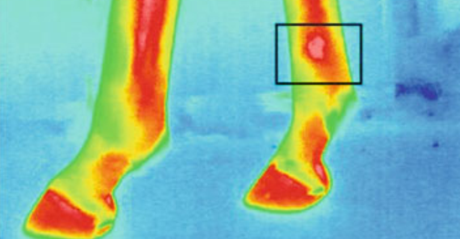

圖為動(dòng)物測(cè)溫儀的馬蹄熱成像

屠宰前動(dòng)物的壓力水平對(duì)肉質(zhì)至關(guān)重要。壓力水平與動(dòng)物的血液和體溫相關(guān)。因此,重要的是監(jiān)視并應(yīng)對(duì)例如溫度升高的溫度。在運(yùn)輸過程中,測(cè)量豬耳朵的溫度,發(fā)現(xiàn)溫度與皮質(zhì)醇的濃度和肌酸激酶的活性呈正相關(guān)。例如,診斷馬匹的行走時(shí),動(dòng)物測(cè)溫儀熱成像會(huì)很有用。建議使用熱成像來檢測(cè)炎癥和其他異常情況,特別是在馬的腿和蹄中。并且也已經(jīng)進(jìn)行了對(duì)諸如蛙等外熱動(dòng)物的熱力學(xué)特性的分析。測(cè)量了從8℃(人工冬眠)到23℃(人工喚醒)加熱過程中青蛙不同身體部位的溫度。在這樣的實(shí)驗(yàn)中,動(dòng)物測(cè)溫儀進(jìn)行測(cè)量而不會(huì)傷害或接觸動(dòng)物是一個(gè)很大的優(yōu)勢(shì)。